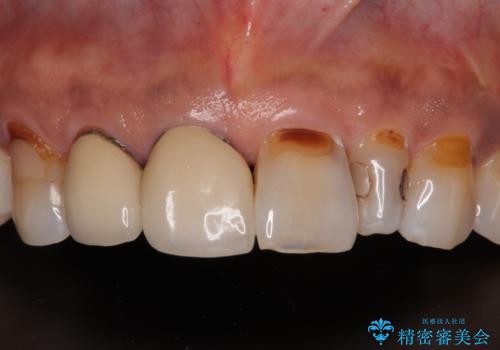

最新の症例